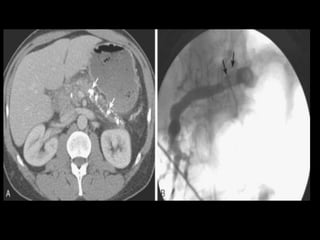

Hemorragia

Artéria esplênica e seus ramos e artérias das

arcadas pancreaticoduodenais.

TC: líquido com alta atenuação na cavidade

peritoneal ou no retroperitônio, numa coleção

líquida preexistente ou num pseudocisto;

Tratamento: angiografia de emergência, com

embolização seletiva.